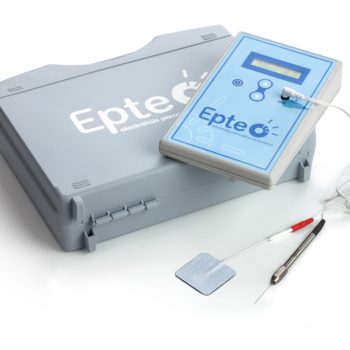

8200.00 złAparat do elektrolizy przezskórnej EPTE®

8200.00 złAparat do elektrolizy przezskórnej EPTE® -